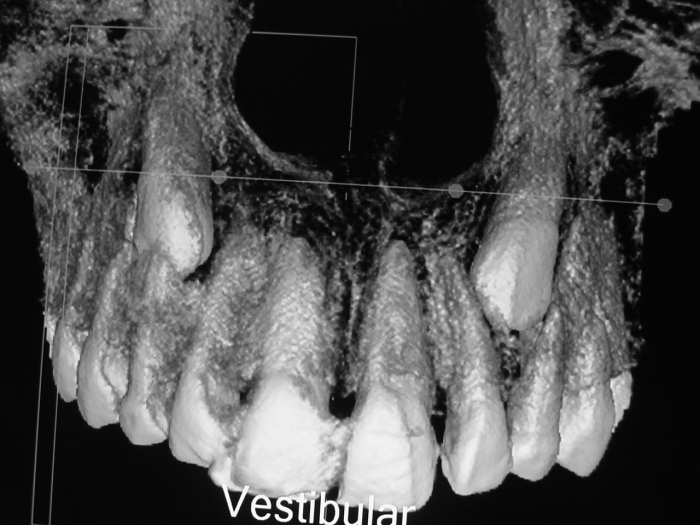

Tomografia - Caninos inclusos e intra-ósseos - Clínica Cliniface

Tomografia - Caninos inclusos e intra-ósseos